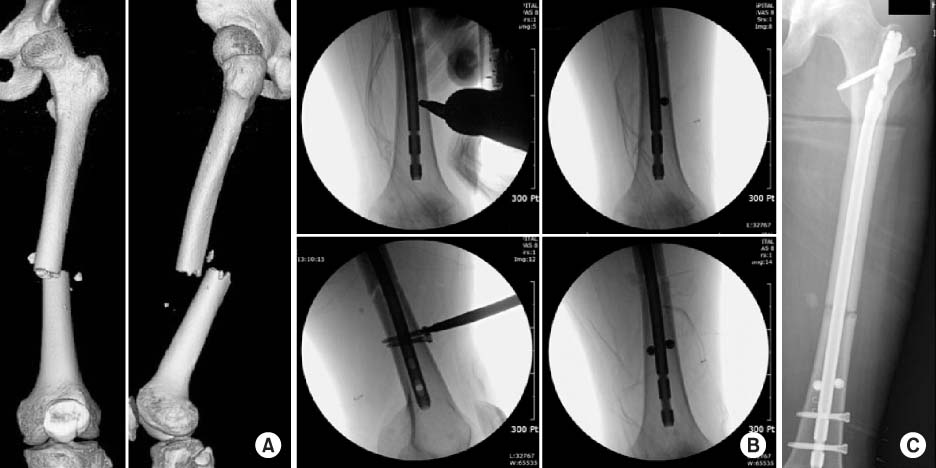

Fig. 2

A 20-year-old male was poly-traumatized after a traffic accident. (A) Anteroposterior radiograph shows an irregular complex femur shaft fracture with a non-displaced fracture of the ipsilateral femoral neck. (B) He underwent damage control-external fixator application at the time of brain surgery in the neurosurgery department. (C) After 3-weeks, he underwent antegrade nailing with two Poller screws after closed reduction with preservation of fracture site biology. Serial radiographs (D: initial postoperative, E: postoperative 2 month, F: postoperative 4 months) show bridging callus progression until radiologic healing.

Fig. 3

(A) Three-dimensional-reconstructed computed tomography images at postoperative 5 months show full consolidation of a complex femur shaft fracture including neck fracture component. (B) However standing lower extremity scanogram shows a limb length discrepancy of 15 mm.

Fig. 2 A 20-year-old male was poly-traumatized after a traffic accident. (A) Anteroposterior radiograph shows an irregular complex femur shaft fracture with a non-displaced fracture of the ipsilateral femoral neck. (B) He underwent damage control-external fixator application at the time of brain surgery in the neurosurgery department. (C) After 3-weeks, he underwent antegrade nailing with two Poller screws after closed reduction with preservation of fracture site biology. Serial radiographs (D: initial postoperative, E: postoperative 2 month, F: postoperative 4 months) show bridging callus progression until radiologic healing.

Fig. 3 (A) Three-dimensional-reconstructed computed tomography images at postoperative 5 months show full consolidation of a complex femur shaft fracture including neck fracture component. (B) However standing lower extremity scanogram shows a limb length discrepancy of 15 mm.